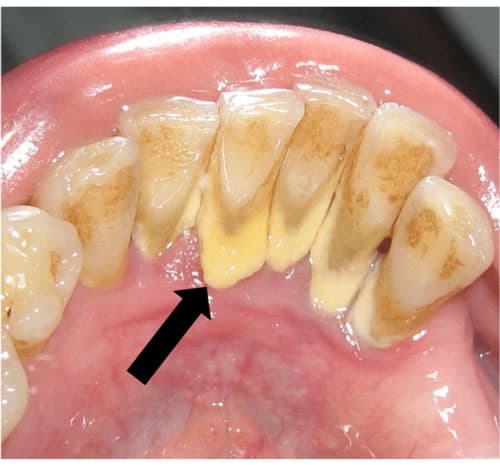

Theo thời gian, mảng bám và các vết thức ăn còn sót lại sẽ tích tụ nhiều lên, trở nên dày hơn ở chân răng và chuyển sang màu vàng đậm. Khi đó, cao răng có thể dày tới khoảng 2mm hoặc hơn. Từ đó gây ra một số vấn đề nhẹ liên quan đến sức khỏe răng miệng. Đây được gọi là mức độ cao răng độ 2 cần quan tâm và xử lý sớm. Nếu không được xử lý kịp thời, tình trạng cao răng có thể trở nên nghiêm trọng hơn. Với cao răng có màu nâu đen, chúng trở nên cứng dày hơn, chứa nhiều vi khuẩn có thể gây ra các vấn đề răng miệng nguy hiểm.

Đầu tiên, cao răng cấp độ 2 có thể gây ra vấn đề thẩm mỹ nghiêm trọng với màu sắc và vẻ ngoại hình của răng. Mảng bám màu vàng đậm bám quanh chân răng có thể khiến bạn cảm thấy không tự tin khi giao tiếp với bạn bè hoặc đối tác.

Cao răng mức 2 màu vàng nhạt đang bám ngay mặt trong của răng và nướu (minh họa).